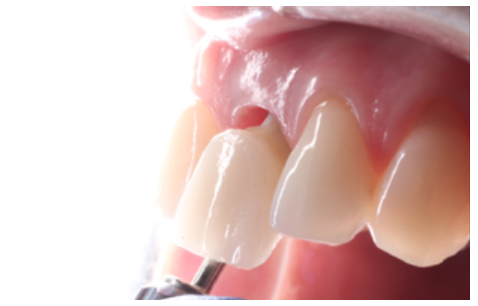

Clinical case: A 32-year-old female patient who attended for a possible root fracture of the upper left central incisor (ULCI), accompanied by a periodontal abscess at the bottom of the vestibule of the same tooth. A clinical and radiological examination established that the prognosis of the ULCI was unfavourable for conservative treatment. After evaluating the clinical features of the case, the treatment plan to extract the ULCI followed immediately by an osseointegrated implant (OII) and loading of a provisional prosthesis on the implant.

Conclusions: Rehabilitation on implants in situations of tooth loss in the aesthetic anterior sector, especially in young patients, requires a multidisciplinary treatment plan to extract the tooth and insert an OII in the correct 3-dimensional position. Various aspects need to be taken into account for this, particularly the residual remaining bone, the position of the gingival margin and preservation and conditioning of the peri-implant hard and soft tissues by means of grafts and proper handling of provisional prosthesis, until an ideal emergence profile and gingival contour is achieved before the final crown.